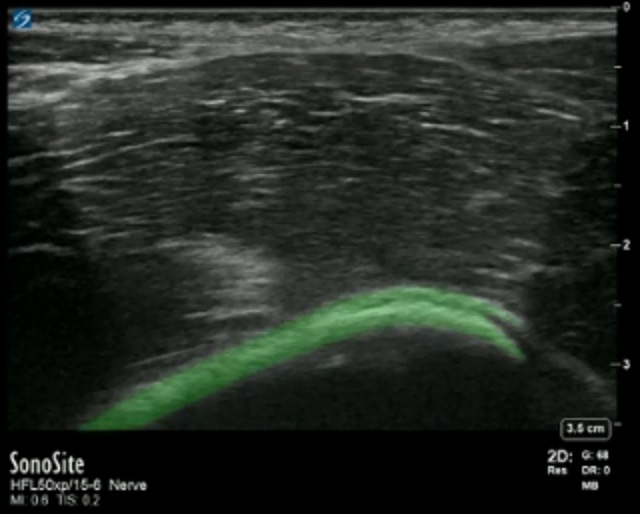

腸骨筋膜平面の強調

左側: 頭蓋

右側: 尾側

強調表示された領域:腸骨